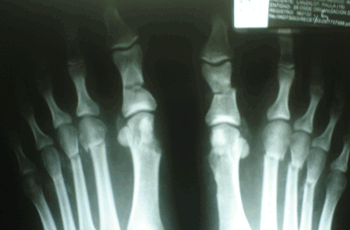

Caso 3: Hallux Valgus del Adulto

Ambos pies operados en el mismo acto quirúrgico.